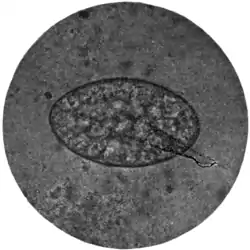

Fig. 168.—Ova of nematodes.

a, Strongylus subtillis; b, Ankylostomum duodenale; c, Trichiuris trichiura; d, Strongyloides starcoralis; e, Necator americanus; f, Ascaris lumbricoides; g, Ascaris lumbricoides (unfertilized).

Ova of Trichiuris trichiura (Fig. 168, c).—Of the three common nematodes mentioned—Trichiuris trichiura, Ascaris lumbricoides, and Ankylostomum duodenale—the ova of the first are the most frequently met with. They occur sometimes in enormous numbers, as many as six or eight specimens being visible in one field of an inch objective. They form a rather striking object under the microscope (Fig. 170). They are oval, measuring 51 to 54 μ by 21 to 23 μ, the ends of the long axis of the oval being slightly pointed and tipped with a little shining projection or plug. Their general appearance suggests an elongated oval tray, the projections at the poles of the ovum representing the handles of the tray. They are dark brown in colour, sharply defined, doubly outlined, and contain no differentiated embryo.

The ova of Ankylostomum duodenale (Fig. 168, b) contrast very markedly with both the foregoing, particularly in the matter of colour. Trichocephalus and ascaris ova are invariably dark and bile-stained; those of the ankylostomum are beautifully clear and transparent; they measure 55 μ to 65 μ by 32 μ to 43 μ; have a regular, somewhat elongated oval form, with a delicate, smooth, transparent shell, through which two, or four, or eight light-grey yolk segments can be distinctly seen. It is well to search for these ova soon after the fæces have been passed; otherwise, owing to the rapidity with which, in favourable circumstances, development proceeds, the embryo may have quitted the shell and the egg be no longer visible.